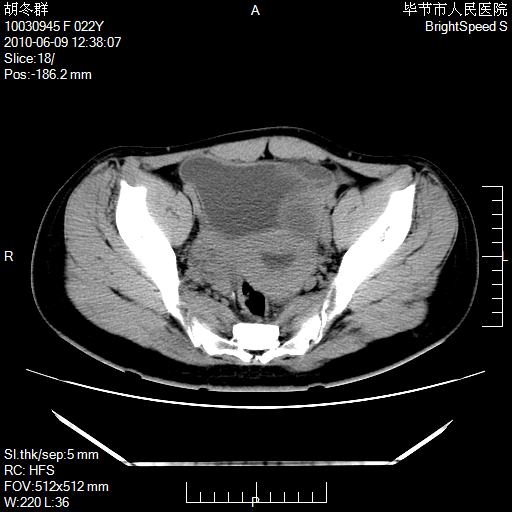

患者23岁,发现腹部包块3月。

盆腔内囊性占位;穿刺或者直接手术拿掉即可,不必紧张。

我当时考虑重复膀胱,但我错得很厉害,我不明白,囊肿排尿后为什么能到膀胱位置。

盆腔内囊性占位性病变;考虑左侧卵巢囊腺瘤。

有分隔、壁薄,支持考虑左侧卵巢囊腺瘤。

左侧卵巢浆液性囊腺瘤。

有分隔、壁薄,支持考虑左侧卵巢囊腺瘤。排尿后,膀胱缩小,由于重力作用,肿块下移就到了膀胱位置,很好理解。